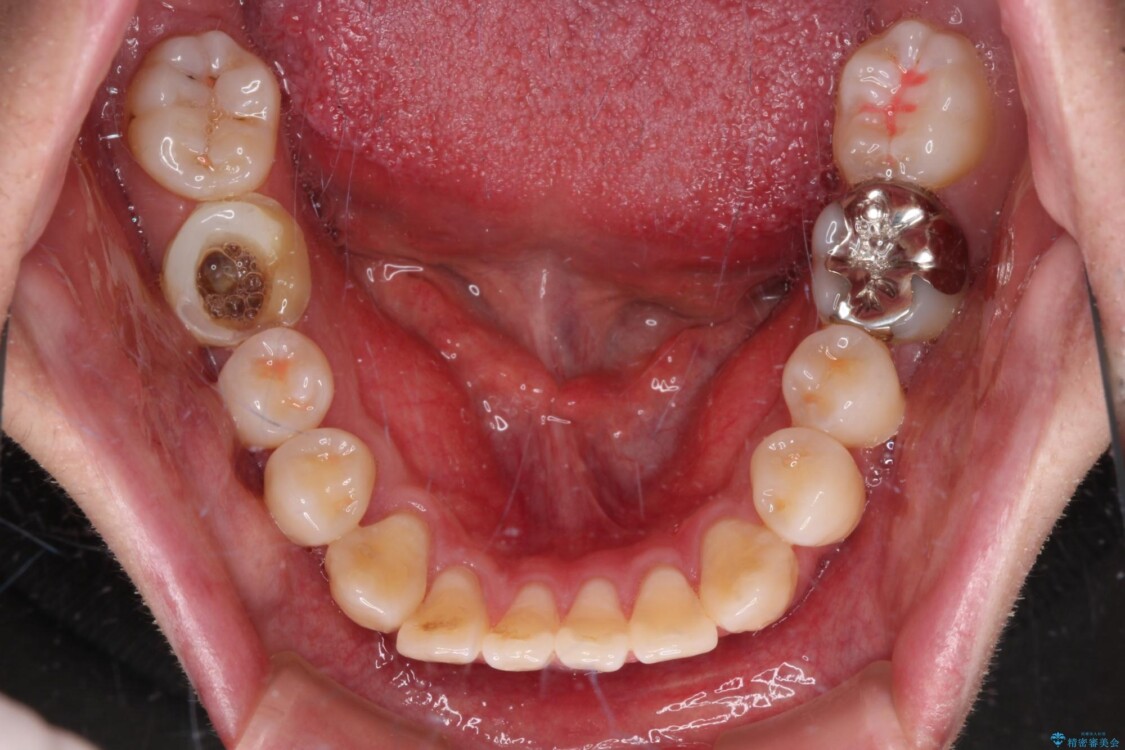

治療前

• 口元の突出感を改善!目立ちにくいワイヤー矯正で自信を持てる自然な横顔に 治療前画像

精密検査の結果、上下左右の小臼歯4本を抜歯し、そのスペースに前歯を後方へ移動させる矯正治療をご提案しました。

「横から見ると唇が前に出て見えるのが気になる…」 「マスクを外すのが恥ずかしい…」 そんな口元の突出感に悩まれてご来院された患者様。